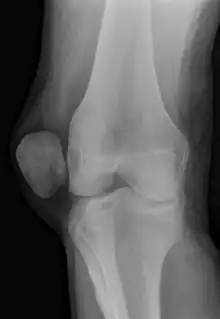

X-ray showing a patellar dislocation, with the patella out to the side. | |

A patellar dislocation is a knee injury in which the patella (kneecap) slips out of its normal position.[5] Often the knee is partly bent, painful and swollen.[1][2] The patella is also often felt and seen out of place.[1] Complications may include a patella fracture or arthritis.[3]

A patellar dislocation typically occurs when the knee is straight and the lower leg is bent outwards when twisting.[1][2] Occasionally it occurs when the knee is bent and the patella is hit.[1] Commonly associated sports include soccer, gymnastics, and ice hockey.[2] Dislocations nearly always occur away from the midline.[2] Diagnosis is typically based on symptoms and supported by X-rays.[2]